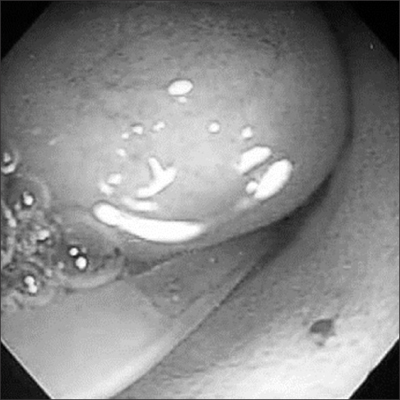

4] and the lumen was hypoechoic. A gastrografin swallow with upper gastrointestinal study demonstrated a mass obstructing the pyloric orifice. A small quantity of gastrografin passed around the perimeter of the lesion and entered the duodenum. Following fluid resuscitation and stabilization, an enteral digestive (ED) tube was inserted on day 7. Magnetic resonance cholangiopancreatography (MRCP) demonstrated that the cystic lesion was located in the pyloric orifice. However, T2-weighted sequences, obtained in the coronal plane did not reveal whether the fluid content of the lesion communicated with the bile duct or not. On day 22, body weight was 2,815 g and an operative exploration was undertaken. A laparotomy was performed through a transverse upper abdominal incision. No cyst was identified, but, an elastic mass was palpable at the pyloric orifice. Intraoperative endoscopy revealed a submucosal gastric lesion approximately 15 mm in size arising from the anterior and inferior surfaces of the pylorus (

Fig. 2). Intraoperative cholangiography documented no communication between the cystic lesion and the bile or pancreatic ducts. Gastrotomy was performed transversally over the antrum just proximal to the cyst, and the cyst was delivered in toto through the incision. The cyst was incised (

Fig. 2Endoscopic view showing the submucosal pyloric lesion approximately 15 mm in size.